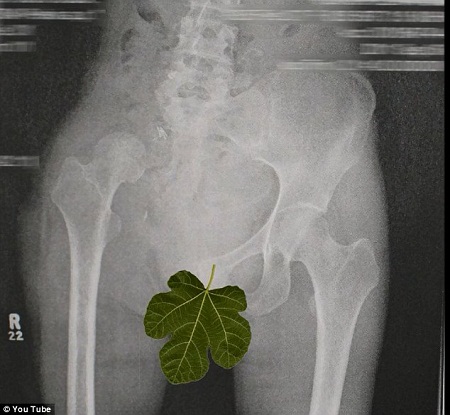

奧謝的手術X光片